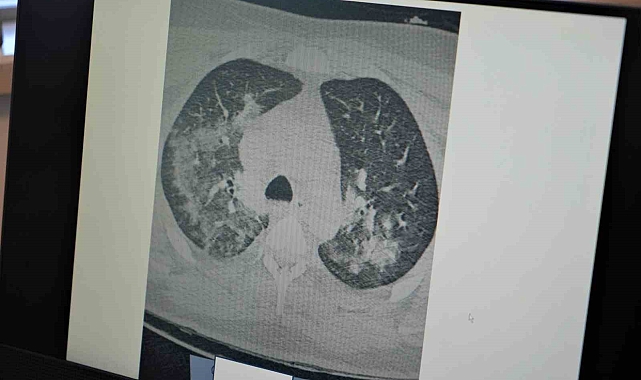

Kovid-19'un damarlarda bıraktığı hasarın önemine dikkat çeken Prof. Dr. Özkaya, "Kovid-19'u yaşadıktan sonra koronanın vücudumuza ne yaptığını öğrendik. Özellikle Kovid-19'dan sonra gerçekten kalp, akciğer ve bütün vücudumuzdaki kılcal damalarımızda hasar oluştu. Bu Kovid-19'un yüküne bağlı olarak sitokin fırtınası dediğimiz bir tablo olan kanın içindeki kan hücreleri taşıyan plazmamızı, kan öz sıvısı öyle tahrip edici hale getirdi ki, damar duvarındaki yapıyı değiştirdi ve bozulmalara neden oldu. Bu durumda pandemi öncesi döneme göre artık damarlarınız da kalıcı hasarlar olabilir. Yaptığınız ağır sporları; halı saha maçı, ağır bisiklet sporları, ağır yüzmeleri pandemi öncesine göre vücudunuz bunları kaldıramayabilir. Hayatı tehdit edici sonuçlar doğurabilir. Ağır sporlar sonrası kalbinizin ve akciğerlerinizin kanını vücudunuz damar hasarı nedeniyle yeterince sağlayamazsa kalp krizleri ve kalp yetmezlikleri ile karşılaşabilirsiniz. Kovid-19 sonrası virüs yükünüze bağlı olarak ortaya çıkan damar duvarındaki değişiklikler kan akımını etkilediği için ağır sporlar sonrası kalp krizleri ve kalp yetmezliği ortaya çıkıyor" diye konuştu.

"Damar embolisi dediğimiz bir tablo var. Bu durumda çok sık görülmeye başladı. Vücuttaki pıhtılaşma probleminin 3 ana sebebi vardır. Birincisi damar duvarı hasarı, ikincisi hareketsiz yaşam, üçüncüsü de genetik yatkınlıktır. Kovid gerçekten pıhtılaşmaya yatkınlık yapan damar duvarı hasarını yaptı. İkinci olan hareketsizlik ise uzun seyahatler, hastalık nedeniyle evde yatmalar sonucu pıhtılaşma oluyor ve buda akciğerlerde damar tıkanıklığına neden oluyor. Bu durum ise ölüme kadar götürüyor. Özellikle sıcak hava ve nemli havalarda ağır sporlarınızı yaparken dikkatli olmanızı öneriyoruz. Gerçekten korona öncesine göre yaptığınız ağır sporlar da vücudunuz sizin kan akışınızı yeterince sağlamayabilir. Uzun süre hareketsiz kalmamanızı öneriyoruz. Özellikle gençlerimizin bu 2 zıt durum olan hem ağır spor hem de hareketsiz yaşama dikkat etmelerini öneriyoruz."